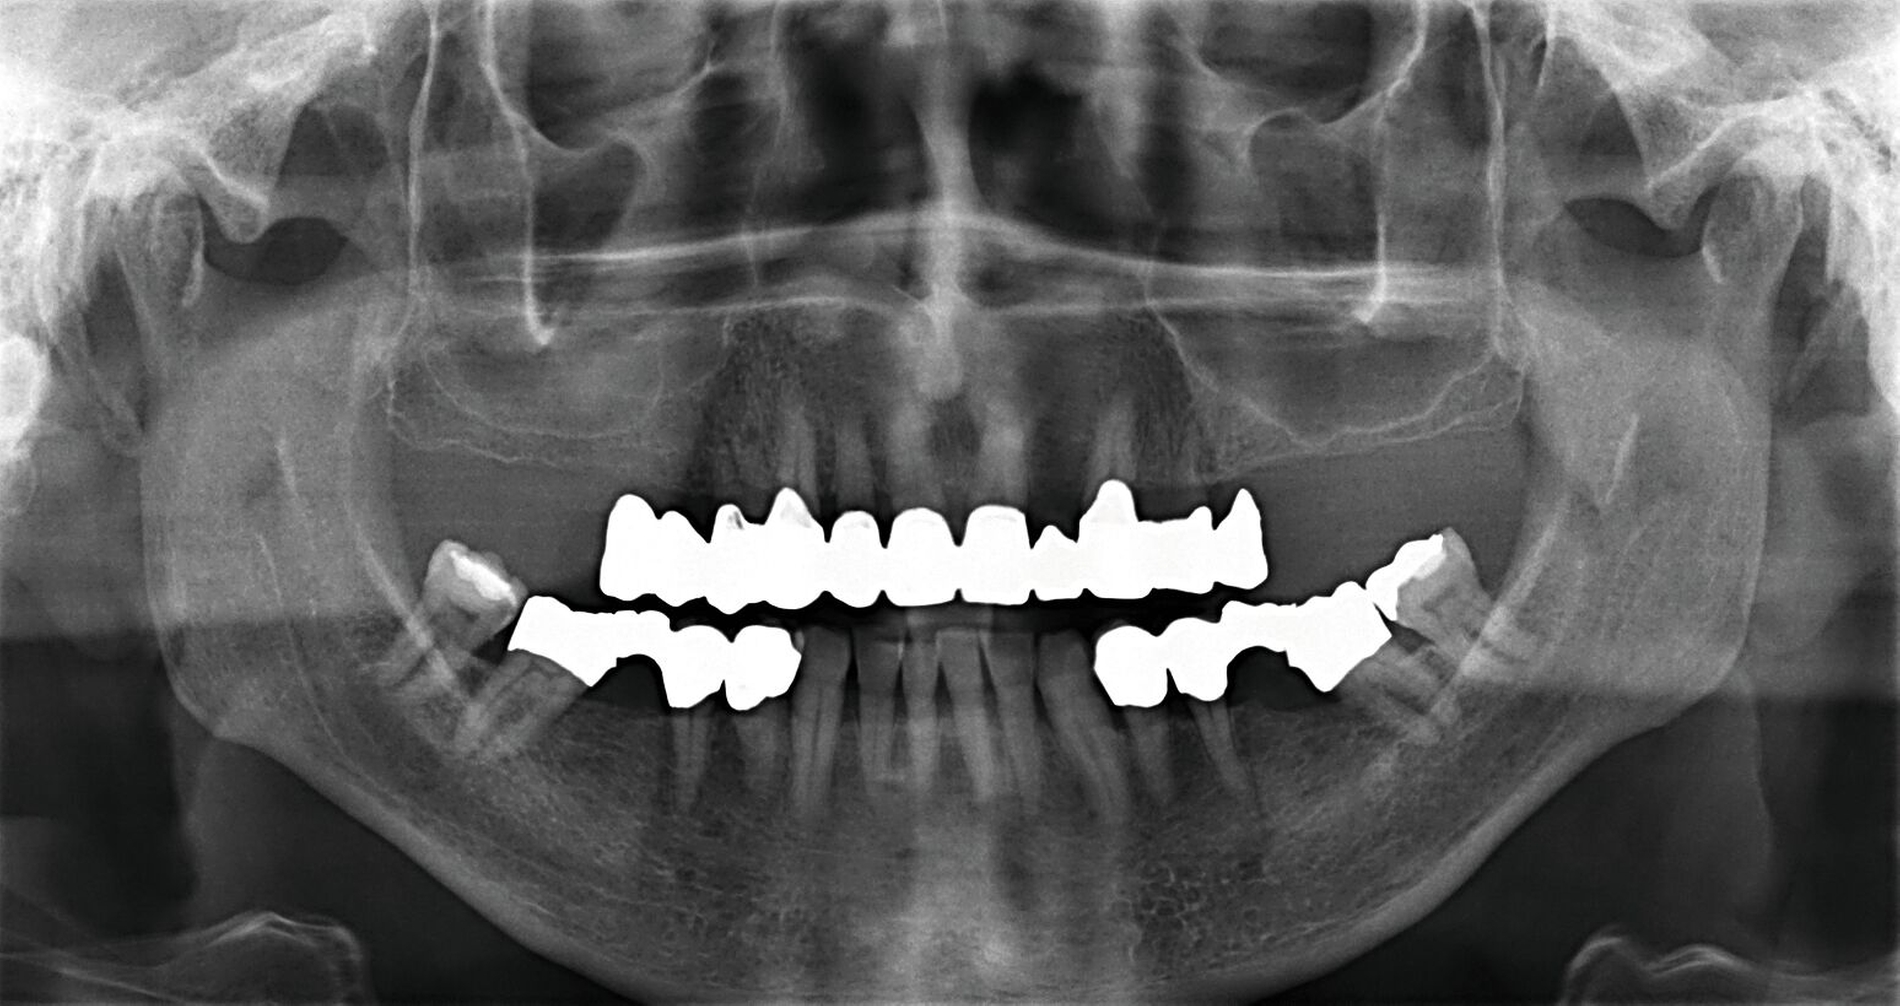

Um den Sitz der Implantatkronen nach dem Einsetzen zu prüfen, wurden intraorale Tubusaufnahmen im Sinne eines Baseline-Röntgens angefertigt (Abbildung 9). In den Folgeterminen wurde dem Patienten noch eine Aufbissschiene für den Oberkiefer eingegliedert, um etwaigem nächtlichen Bruxismus vorzubeugen. Für die Nachsorge empfiehlt sich ein halbjährliches Kontrollintervall.

Der Fall zeigt einen sehr hohen Behandlungsaufwand mit einer Behandlungsdauer von etwa zwei Jahren (Abbildung 10). Auf zum Teil notwendige endodontische Behandlungen wurde hier aus Gründen der Übersichtlichkeit nicht näher eingegangen.